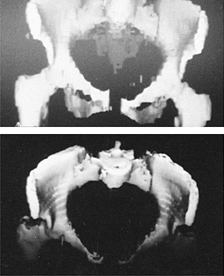

![]() |

Figure 28.21. Modified Salter innominate osteotomy. Note that the block of bone actually opens the posterior cortex.